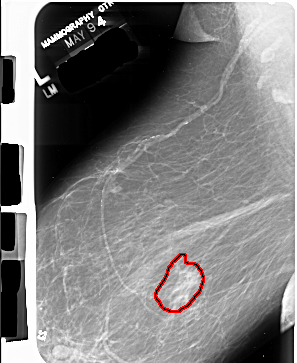

FILE: A_1014_1.LEFT_MLO.OVERLAY

TOTAL_ABNORMALITIES 1

ABNORMALITY 1

LESION_TYPE MASS SHAPE IRREGULAR MARGINS ILL_DEFINED

ASSESSMENT 4

SUBTLETY 4

PATHOLOGY MALIGNANT

TOTAL_OUTLINES 1

BOUNDARY

LEFT_MLO LINES 6886 PIXELS_PER_LINE 5641 BITS_PER_PIXEL 16 RESOLUTION 42 OVERLAY